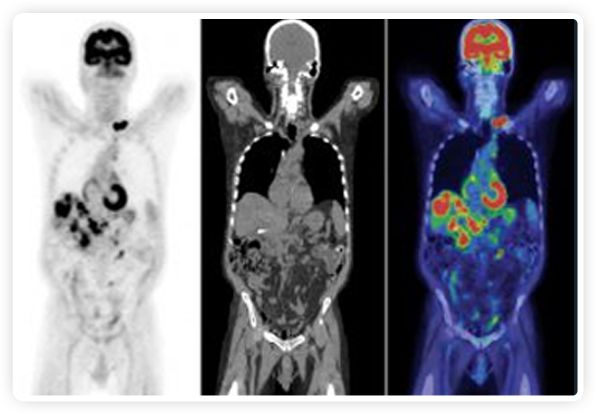

RefleXion將PET成像與立體定向放射治療相結(jié)合。在注射示蹤劑后,RefleXion的技術(shù)基于示蹤劑信號實時地在一個或多個目標上引導治療性X射線。使用這種專有方法,RefleXion的平臺有可能比現(xiàn)有系統(tǒng)向癌癥病變提供更高劑量的輻射,并改善周圍健康組織的保護。

為了避免PET長圖像采集時間,RefleXion開發(fā)了一項專利技術(shù)使用重合的PET光子對來指導放射治療束,因為實時檢測發(fā)射的光子,為生物指導提供了一種時間有效的方法。